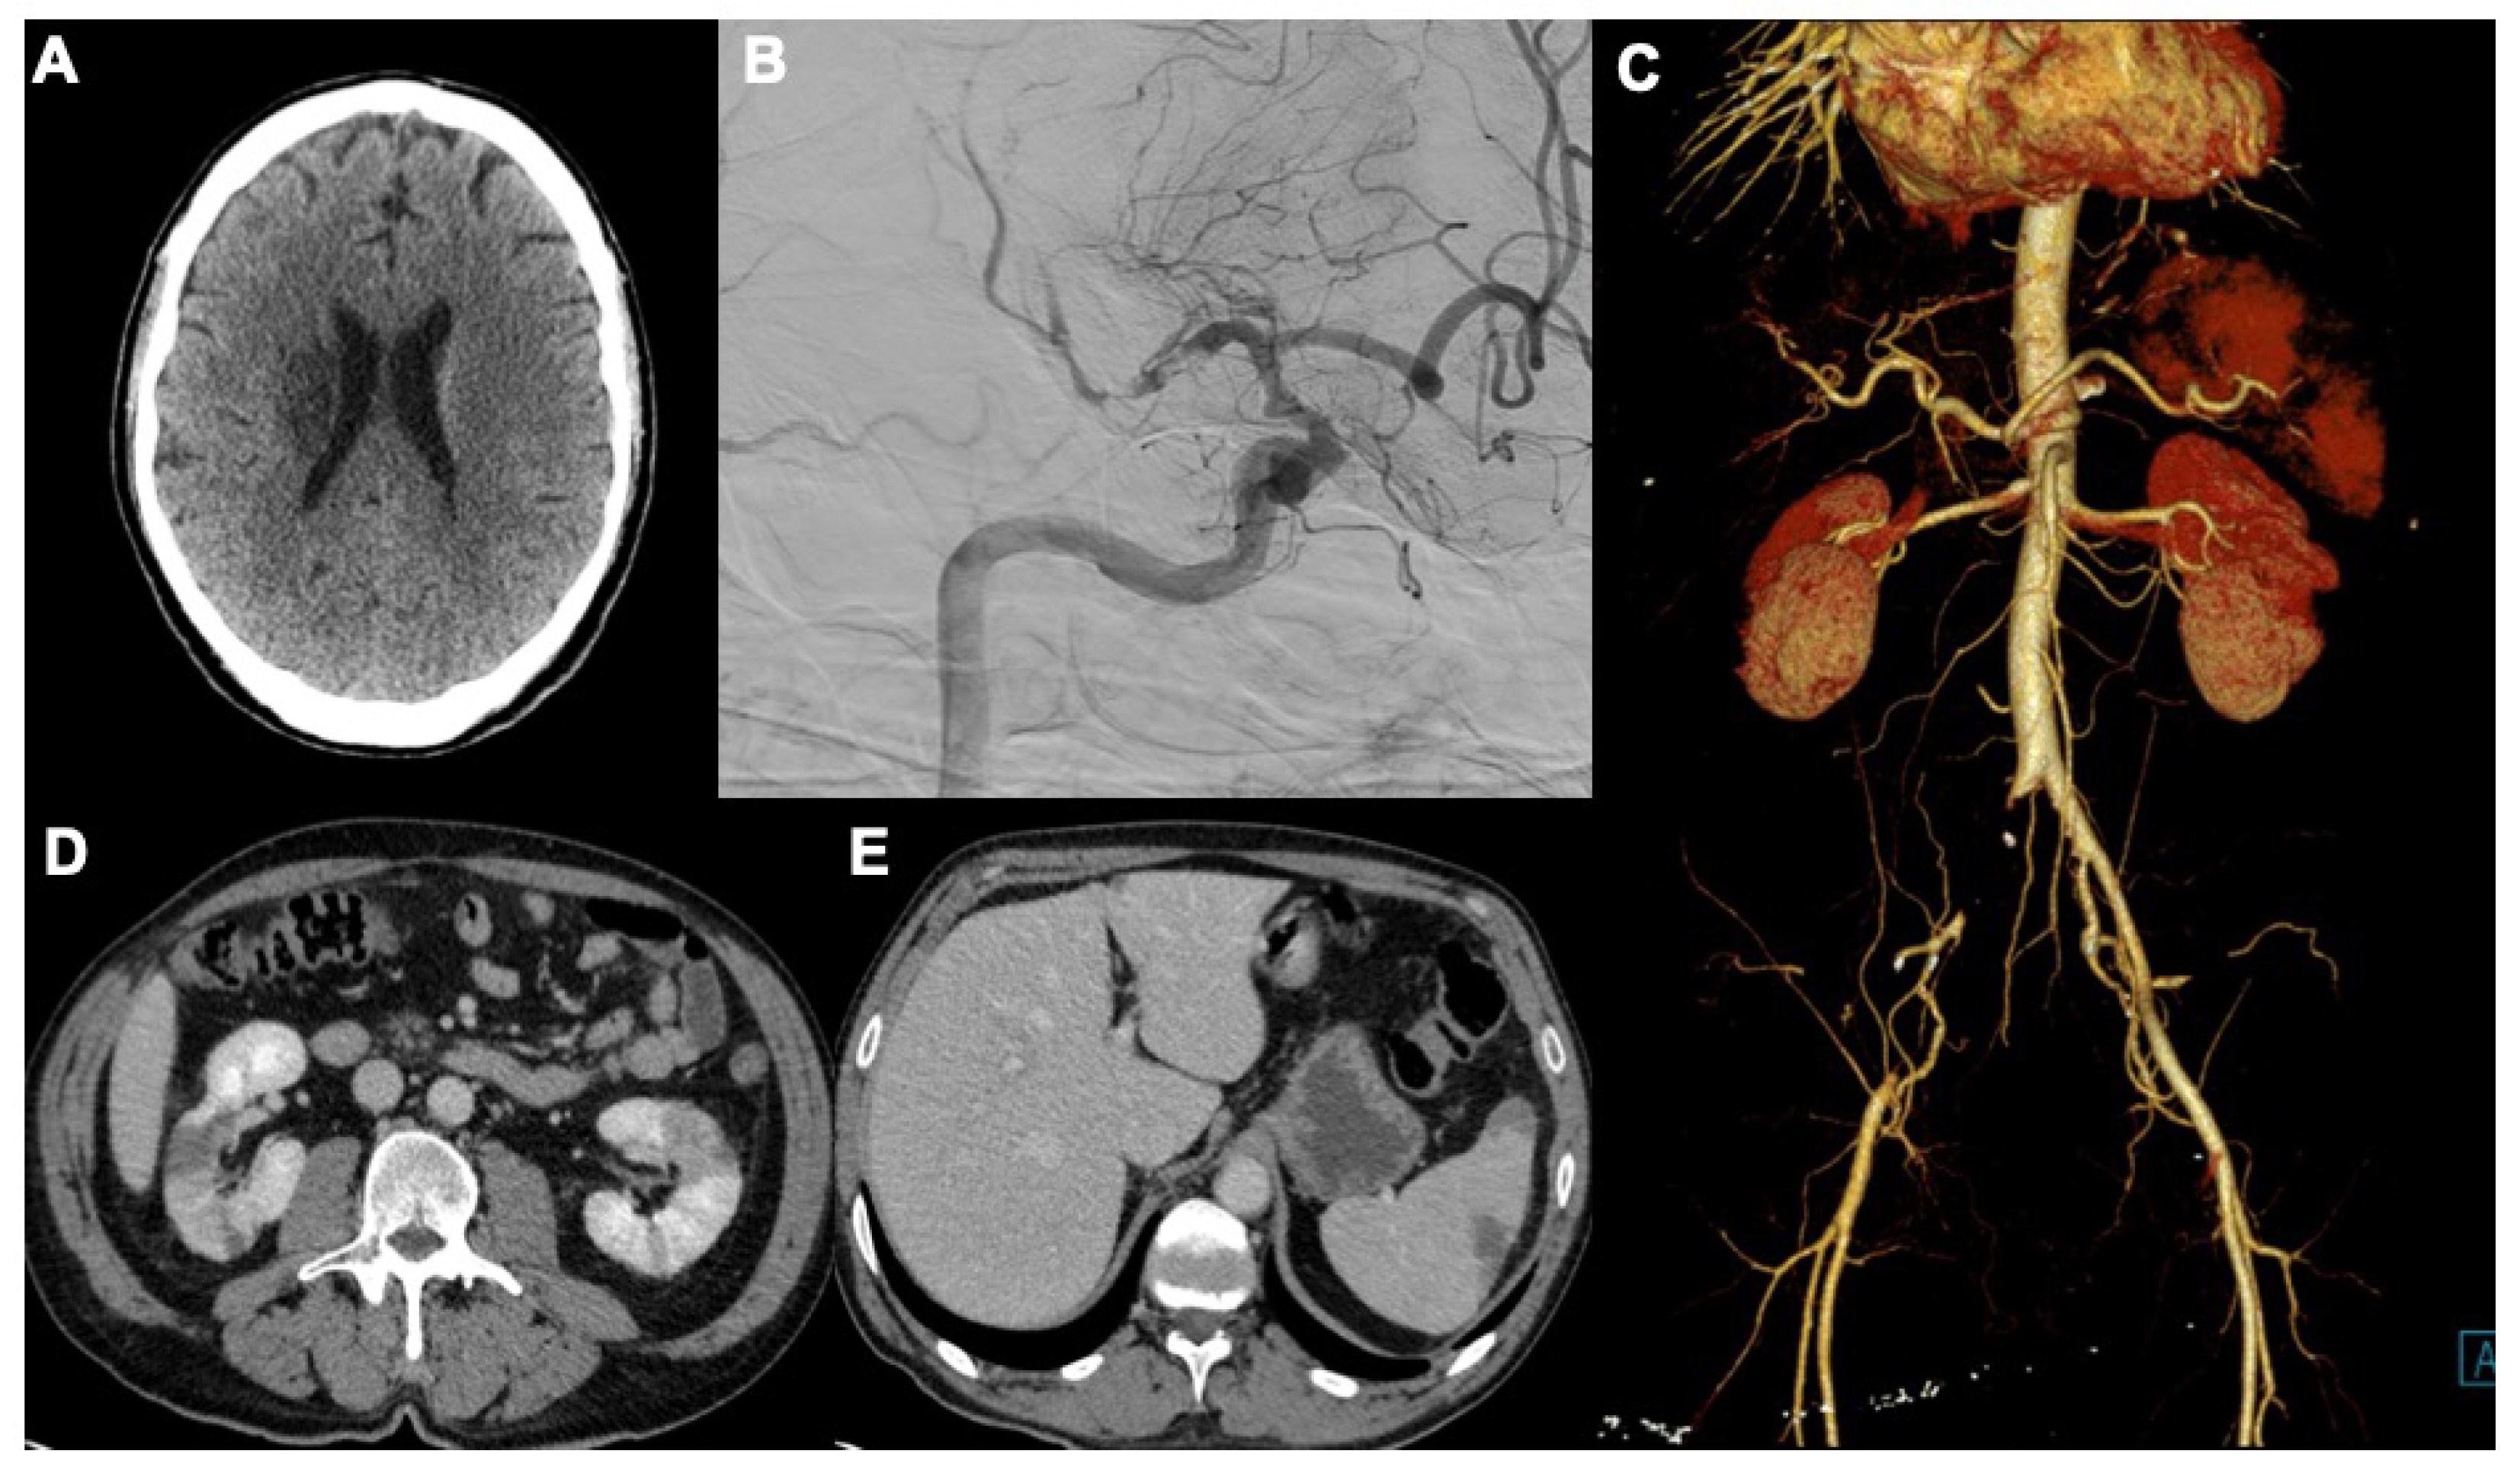

3. COVID-19 and Extrapulmonary Manifestations

3.1. Neurological Findings

3.2. Cardiac Manifestations

3.3. Abdominal Manifestations